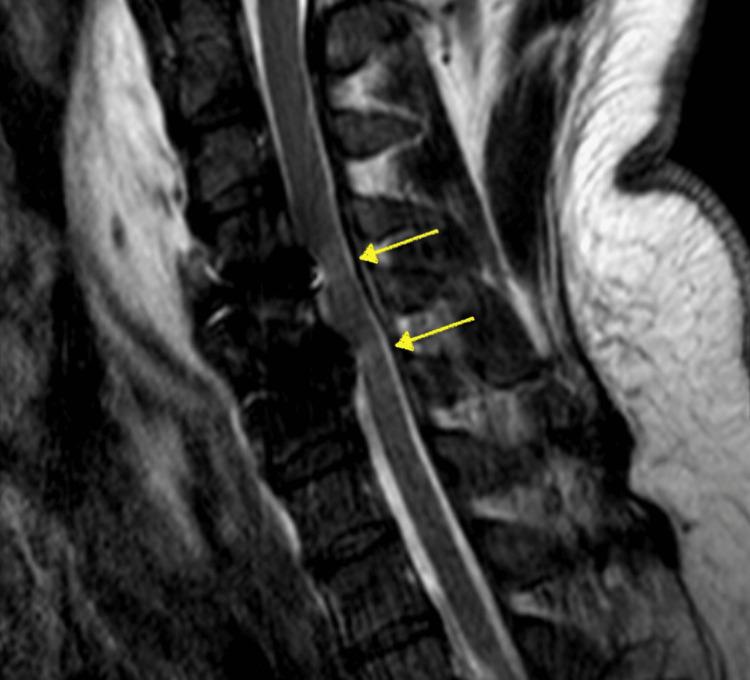

Cervical myelopathy is a progressive degenerative condition characterized by spinal cord compression, which often requires surgery to avoid further stepwise deterioration of this pathology. While anterior cervical discectomy and fusion (ACDF) is a well-established treatment, postoperative neurological deficits, although rare, remain a significant concern. White cord syndrome (WCS) is an uncommon cause of acute neurological deficit following spine surgery that is attributed to a reperfusion injury following decompression of a chronically impinged spinal cord. We present the case of a 47-year-old male with a preoperative diagnosis of cervical myelopathy (Nurick 4) who developed acute quadriplegia following ACDF. Initial imaging ruled out common postoperative complications, such as hematoma or hardware malposition, and an MRI revealed hyperintense signals consistent with WCS. Supportive management led to partial neurological recovery by postoperative day 3, followed by complete neurological recovery and marked functional and strength improvement beyond baseline by the five-month follow-up. This report aims to present a case of WCS, a rare complication following spinal decompression surgery, highlighting its diagnosis, management, and outcome.

脊髓型颈椎病是一种以脊髓受压为特征的进行性退行性疾病,通常需要手术治疗以避免该病理状况进一步逐步恶化。虽然颈椎前路椎间盘切除融合术(ACDF)是一种成熟的治疗方法,但术后神经功能缺损虽然罕见,仍是一个重大问题。白脊髓综合征(WCS)是脊柱手术后急性神经功能缺损的罕见原因,归因于长期受压脊髓减压后的再灌注损伤。我们报告一例47岁男性患者,术前诊断为脊髓型颈椎病(Nurick 4级),在ACDF术后出现急性四肢瘫痪。初步影像学检查排除了常见的术后并发症,如血肿或内固定位置不当,MRI显示与WCS一致的高信号。支持性治疗使患者在术后第3天部分神经功能恢复,随后完全恢复神经功能,并且在五个月的随访中,功能和力量明显改善,超过基线水平。本报告旨在介绍一例WCS病例,这是脊柱减压手术后的罕见并发症,重点强调其诊断、治疗及结果。